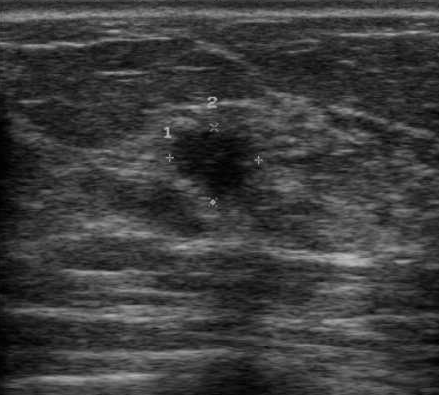

The target dataset was developed from 35 breast ultrasound scans that were segmented by an image-processing expert with extensive experience in breast lesion segmentation (the second author). The images, collected from the Web, are of different dimensions, ranging from to pixels (Figure 3, images resized for sake of illustration). These are the same images used to introduce EFIS originally [1].

Ultrasound images are generally difficult to segment, primarily due to the presence of speckle noise and low level of local contrast. It should be noted that the segmentation of ultrasound actually does require a complete processing chain, (including proper preprocessing and post-processing steps). However, the purpose of using these images was solely to demonstrate that the accuracy of the segmentation can be increased with the application of SC-EFIS.